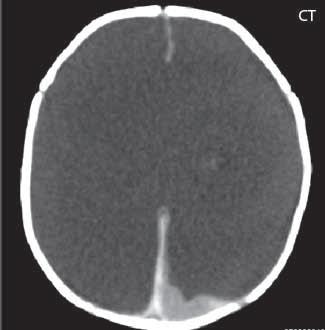

Při agenezi corpus callosum CT i MR zobrazí paralelní průběh postranních mozkových komor (oproti fyziologickému

konvergentnímu průběhu) a jejich oddálení, časté rozšíření okcipitálních rohů – colpocefalie, někdy středočárový lipom, cystu. Koronální řezy ukážou rozšíření frontálních rohů postranních komor, III. komora je situována vysoko mezi postranní komory, tvoří jakoby trojzubec, který někteří autoři přirovnávají k přilbě Vikinga. Není patrné septum pellucidum. Častá je přítomnost středočárového lipomu nebo cysty.

Obr. I.1.2a Paralelní postavení postranních komor, kolpocefalie, ageneze corpus callosum

Obr. I.1.2b Ageneze corpus callosum

Obr. I.1.2c Ageneze corpus callosum, frontální rohy postranních komor mají tvar rohů na Vikingské helmě, kraniálně uložená III komora